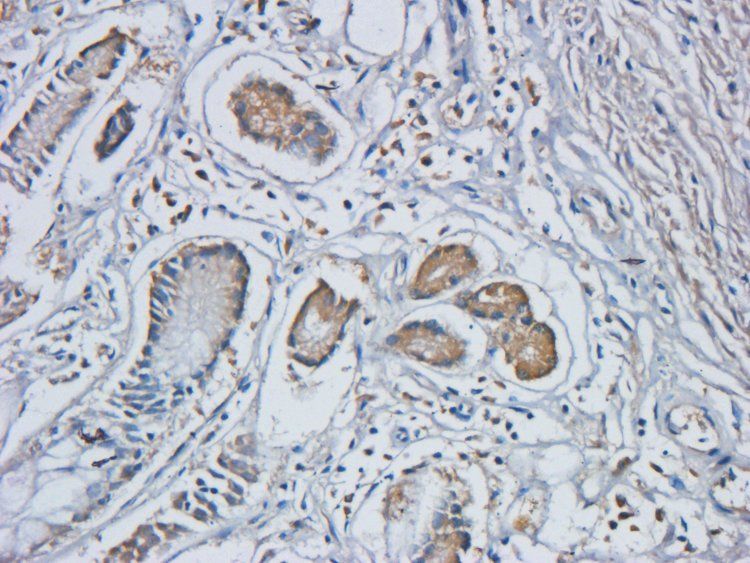

应用稀释比例:IHC-P:1:200, WB: 1:500, IF/ICC: 1:200

ELISA, ICC, IF, IHC-P, WB